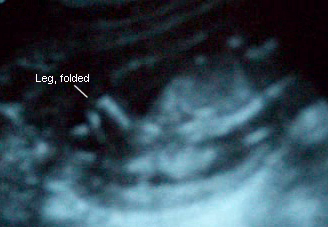

Sono Pic:

15 weeks, 6 days:

September 16th: My actual appointment wasn’t till the next day, the 17th, but I’d developed a nasty UTI so I went in a day early. Dr. prescribed some antibiotics, even though he said there was hardly any trace of infection, but I felt awful! My blood pressure and glucose were fine, even after having coffee for breakfast! The Dr. measured the baby and then tried determining the gender…but baby wouldn’t let us see! The little legs were crossed and he/she wouldn’t move them! The Dr. even jiggled my belly back and forth with the wand to wake the baby up, but it just wiggled a little and continued to slumber! Would go back in 2 weeks for the AFP, so we’d check again then.